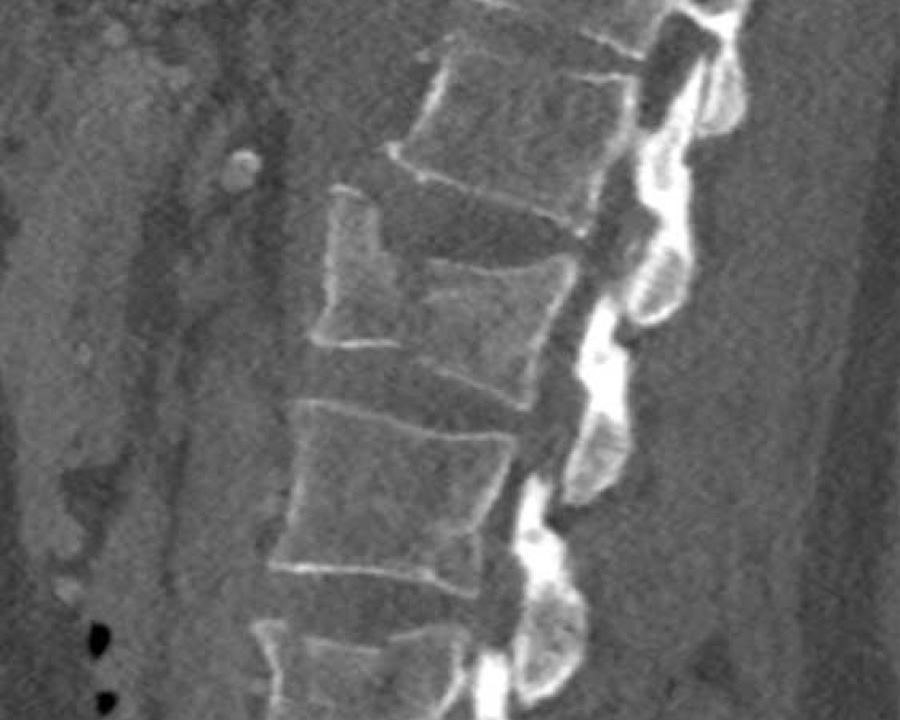

Here more examples of typical burst injuries.

Due to the axial force, the vertebral body is ‘split in half’, therefore a sagittal course of the fracture is common.

Therefore a fracture through the posterior osseous structures is possible in some type A injuries and should not always be regarded as a posterior distraction injury.

This can be confusing sometimes.

A3 Incomplete Burst fractures

Fracture with any involvement of the posterior wall; only a single endplate fractured.

A vertical fracture of the lamina is usually present and does not constitute a tension band failure.